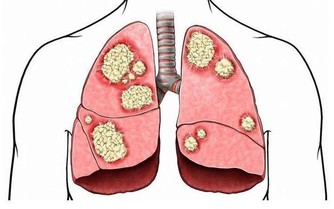

8、預防大腸癌

富含水溶性膳食纖維,能保護腸胃,「預防大腸癌」。